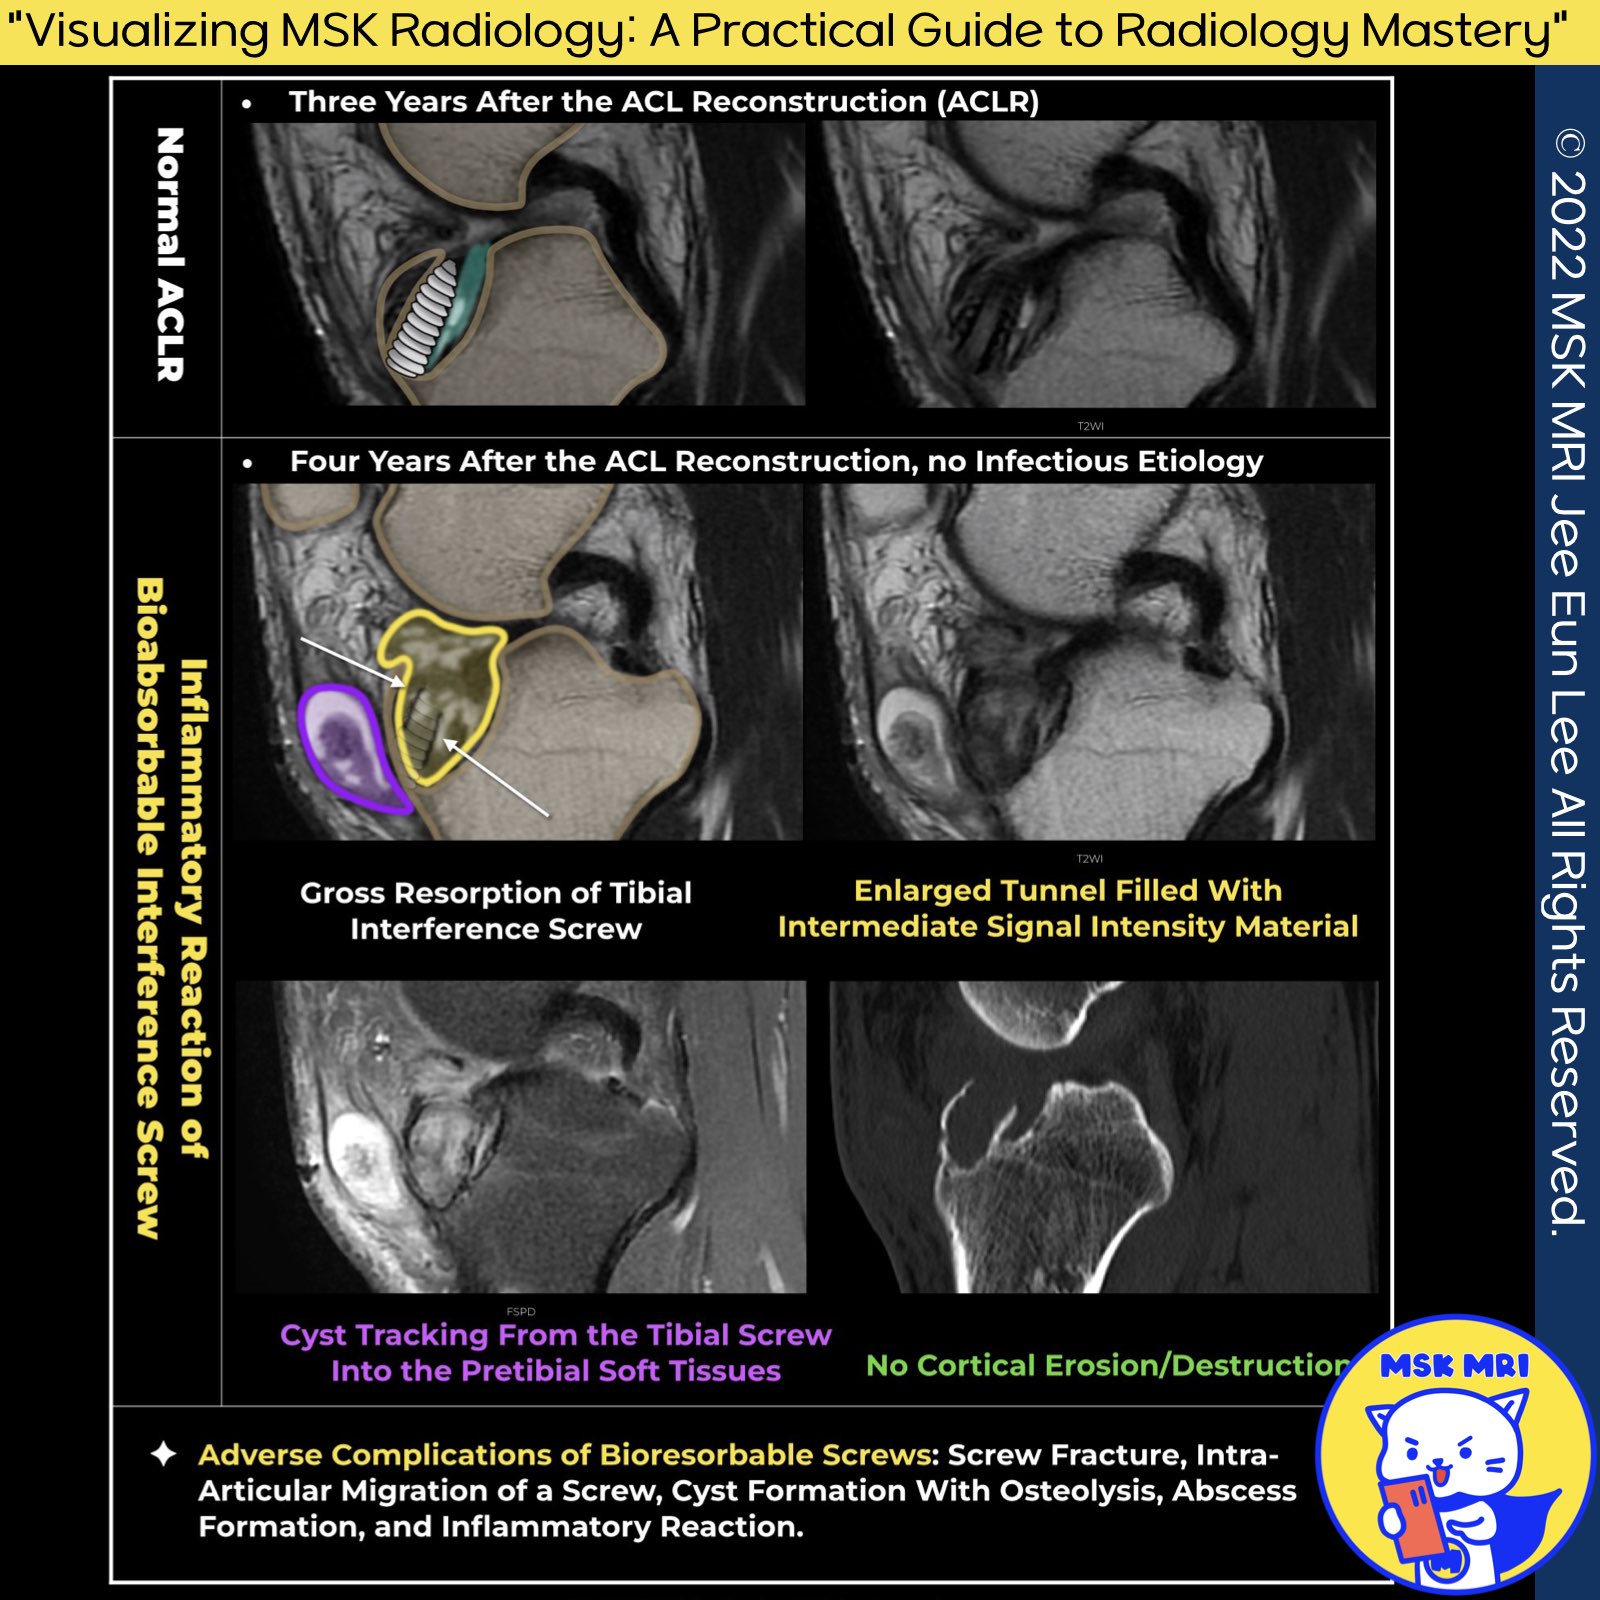

1️⃣ Bioabsorbable Screw

- The primary role of the bioabsorbable screw is to secure the graft and maintain stable fixation long enough for the graft to integrate fully before the screw begins to degrade.

2️⃣ Graft Incorporation vs. Screw Degradation

- Timing Mismatch: A disparity between the time needed for graft incorporation and the rate of screw degradation can lead to complications.

- Rapid degradation: → Cyst development

- Delayed → Lack of bony integration

3️⃣ Delayed Foreign Body Reactions to Bioabsorbable Pins

✅ Reactions to Poly-L-lactic Acid (PLLA) Implants

- Pretibial Complications: Sterile abscess and subcutaneous pretibial ganglion formation.

- Inflammatory Responses: Delayed intra-articular inflammatory reactions, leading to tibial and pretibial cyst formation.

- Synovial Reactions: Aseptic synovitis and foreign body gonitis (knee inflammation).

- Bone Reactions: Osteolytic foreign body reaction, where the body's reaction to the implant leads to bone dissolution.

✅ Reactions to Polyglycolic Acid (PGA) Implants

- Bone Reactions: Osteolytic foreign body reaction similar to PLLA implants.

- Synovial Reactions: Aseptic synovitis, involving the synovial membrane.

- Immune Responses: Specific immune responses to the PGA material, potentially leading to inflammation and other complications.